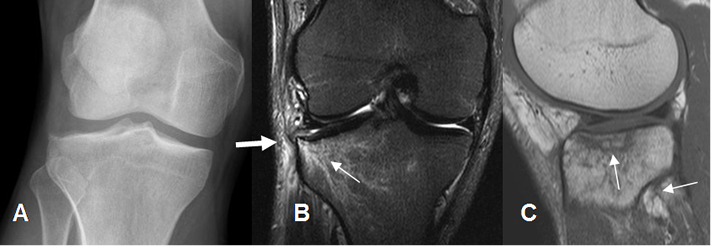

Fig 38. Fractura de la microtrabécula.

A: Rx AP. Sin signos claros de lesión traumática.

B: RM coronal en STIR. Edema óseo sobre el platillo tibial lateral (Flecha delgada) y cambios inflamatorios en los tejidos blandos. (Flecha gruesa).

C: RM sagital en T1. Fractura en la microtrabécula sobre el platillo tibial y la cabeza del peroné.